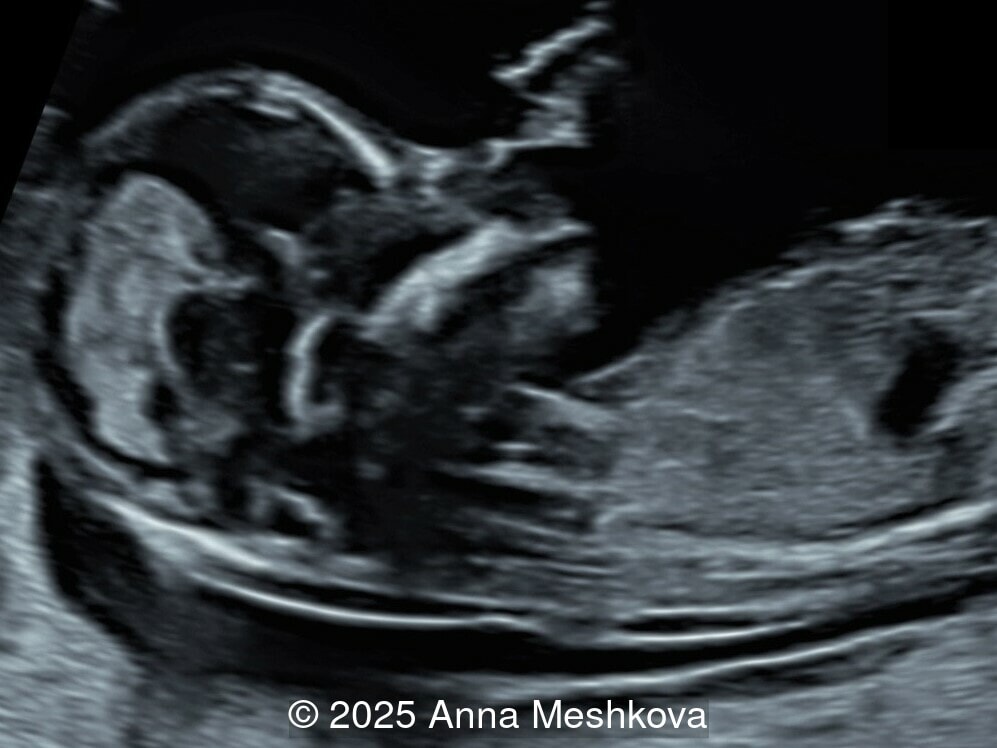

• Image 3, Video 1: Mid-sagittal image demonstrating the mid brain and brain stem displaced posteriorly, known as the "crash" sign. Intracranial translucency is difficult to visualize.

5.  The Crash Sign describes the posterior displacement and deformation of the mesencephalon against the occipital bone due to reduced intracranial pressure caused by cerebrospinal fluid leakage. This is a promising early marker seen in a majority of first-trimester open spina bifida cases.  During this posterior displacement, the mesencephalon meets the only firm cranial structure on its way, the occipital bone, and is compressed against it.  On mid-sagittal view the brainstem is thickened and shifted posteriorly [6].

In spina bifida, the midbrain is posteriorly displaced, eliminating the space between the cerebral peduncles and the occipital bone. The transition between the cerebral peduncles and thalami appears as two parallel lines instead of the normal acute angle

Image 12 In spina bifida, the midbrain is posteriorly displaced, eliminating the space between the cerebral peduncles and the occipital bone. The transition between the cerebral peduncles and thalami appears as two parallel lines instead of the normal acute angle